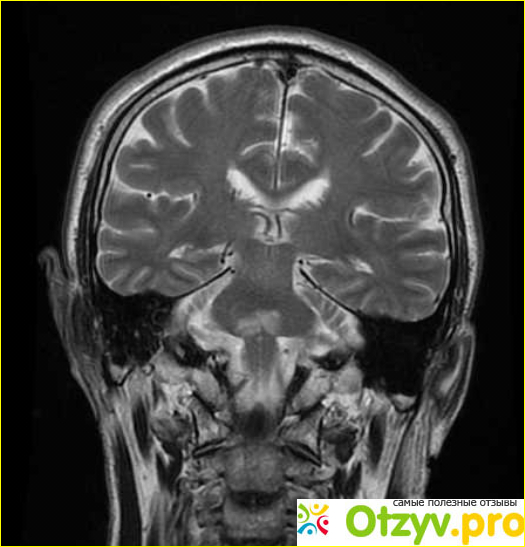

От такого диагноза даже мне стало не по себе, я стала интересоваться у врачей что же это такое, есть ли опасность для других детей. Теперь я расскажу что же мне пояснили врачи. Ли капать очень часто наблюдается у недоношенных детей. Возможно ещё в утробе у матери у ребенка было кислородное голодание, когда мозгу не хватает кислорода, то некоторые его ткани просто отмирают. Также и кислородное голодание, приводит к разжижению какого-то там вещества в головном мозге. В особой зоне риска находятся как раз недоношенные дети. Ну такое заболевание может проявиться и на более поздних сроках, а не в первые дни после рождения. Это заболевание очень сложно диагностировать. Но врачи, уделяют особое внимание недоношенным деткам. Поэтому Удалось сделать диагностику заболеваний в первые дни его жизни.

Основными симптомами являются угнетенное состояние нервной системы, а также судороги. У маленьких детей это может быть ещё и затрудненность глотания, может быть нарушена дыхательная система. К сожалению полностью вылечить лейкопатия невозможно. Потому что некоторые ткани головного мозга уже неживые, Единственное что можно сделать в этом случае это просто устранить симптомы.

Случается не только у детей. Например среди взрослых людей могут быть подвержены ему Те у кого ВИЧ, а может быть какие-то заболевания крови. В общем всё то, что снижает иммунитет, и мешает нормальному притоку крови к головному мозгу. Взрослых это также проявляется, как он маленьких детей. Это может быть нарушение координации движений, неправильная речь, может отразиться даже на зрение, иногда даже случаются приступы, похожие на эпилепсию. Естественно у взрослых Это постоянная головная боль.